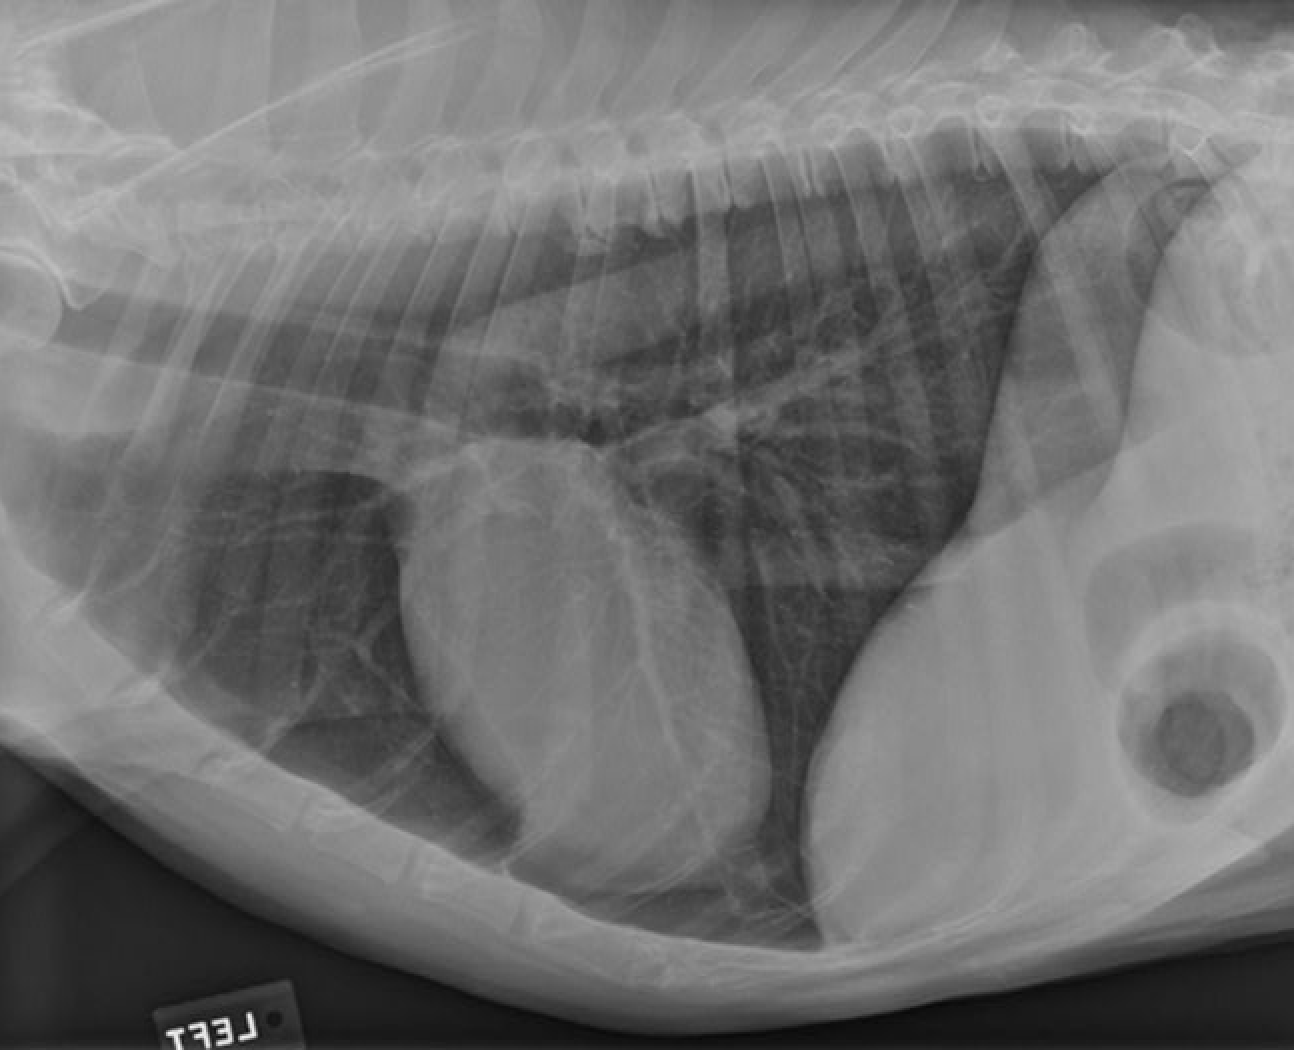

identity the structures on the thorax radiograph left lateral view

identify the right cranial lung lobe

identify the right cranial bronchus

identify the right accessory lobe of the lung

identify the right crus of the diaphragm

identify the left crus of the diaphragm

identify the dome of the diaphgram

identify the left cranial lung lobe

identify the structures

identify the pulomary arteries

identify the aorta

identify the ventral mediastiunum

identify the scapula

identify the ventral lung lobes